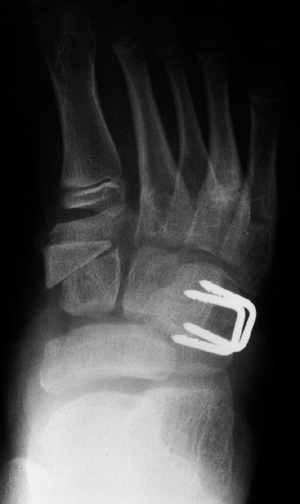

![]() |

Figure 30.14 A: Valgus deformity of the hindfoot is a complication of clubfoot management resulting in weak push-off and pain. B: Computed tomography (CT) scan is used to evaluate the deformity and the subtalar joint.

|

instability, in which division of the interosseous ligament as well as

release of the subtalar joint may result in lateral translation of the

calcaneus under the talus, as shown by Simons (90).

Although complete subtalar release has been recommended by some,

overcorrection of the hindfoot into a valgus position is one of the

complications that can result from this procedure.

produce hindfoot valgus, in that as a patient bears weight, the

for rigid forefoot supination that may drive the hindfoot deformity.

deformity of hindfoot valgus in general. A CT scan will allow

evaluation of the subtalar joint as well as the alignment of the

hindfoot deformity. Also, be aware that valgus may result from the

tilting of the distal tibial articular surface.

calcaneal translational osteotomy as well as calcaneal lengthening, and

finally, subtalar arthrodesis. In severe cases, triple arthrodesis may

be necessary. In a calcaneal slide osteotomy, the tuberosity of the

calcaneus is shifted medially, generally from the lateral approach,

with the calcaneal osteotomy just posterior to the posterior facet of

the subtalar joint. In order for the procedure to work, a competent

subtalar joint must be present and is best evaluated using a CT scan (Fig. 30.14B).